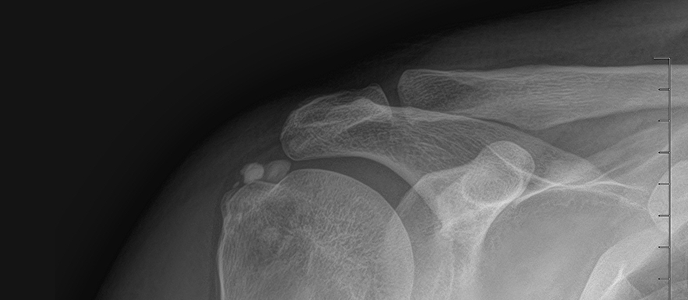

석회쇄석술 전후사진

치료 증상 갑자기 팔 들기 힘듦, 밤에 아픔

나이/성별 55세 / 남성

치료 내용 석회쇄석흡인술 후 호전

치료 기간 2024-11-22 ~ 2025-02-22

※ 해당 사진은 수정없는 실제 치료사진입니다. 환자의 치료결과는 환자의 상태, 치료방법 등에 따라 차이가 발생할 수 있습니다.